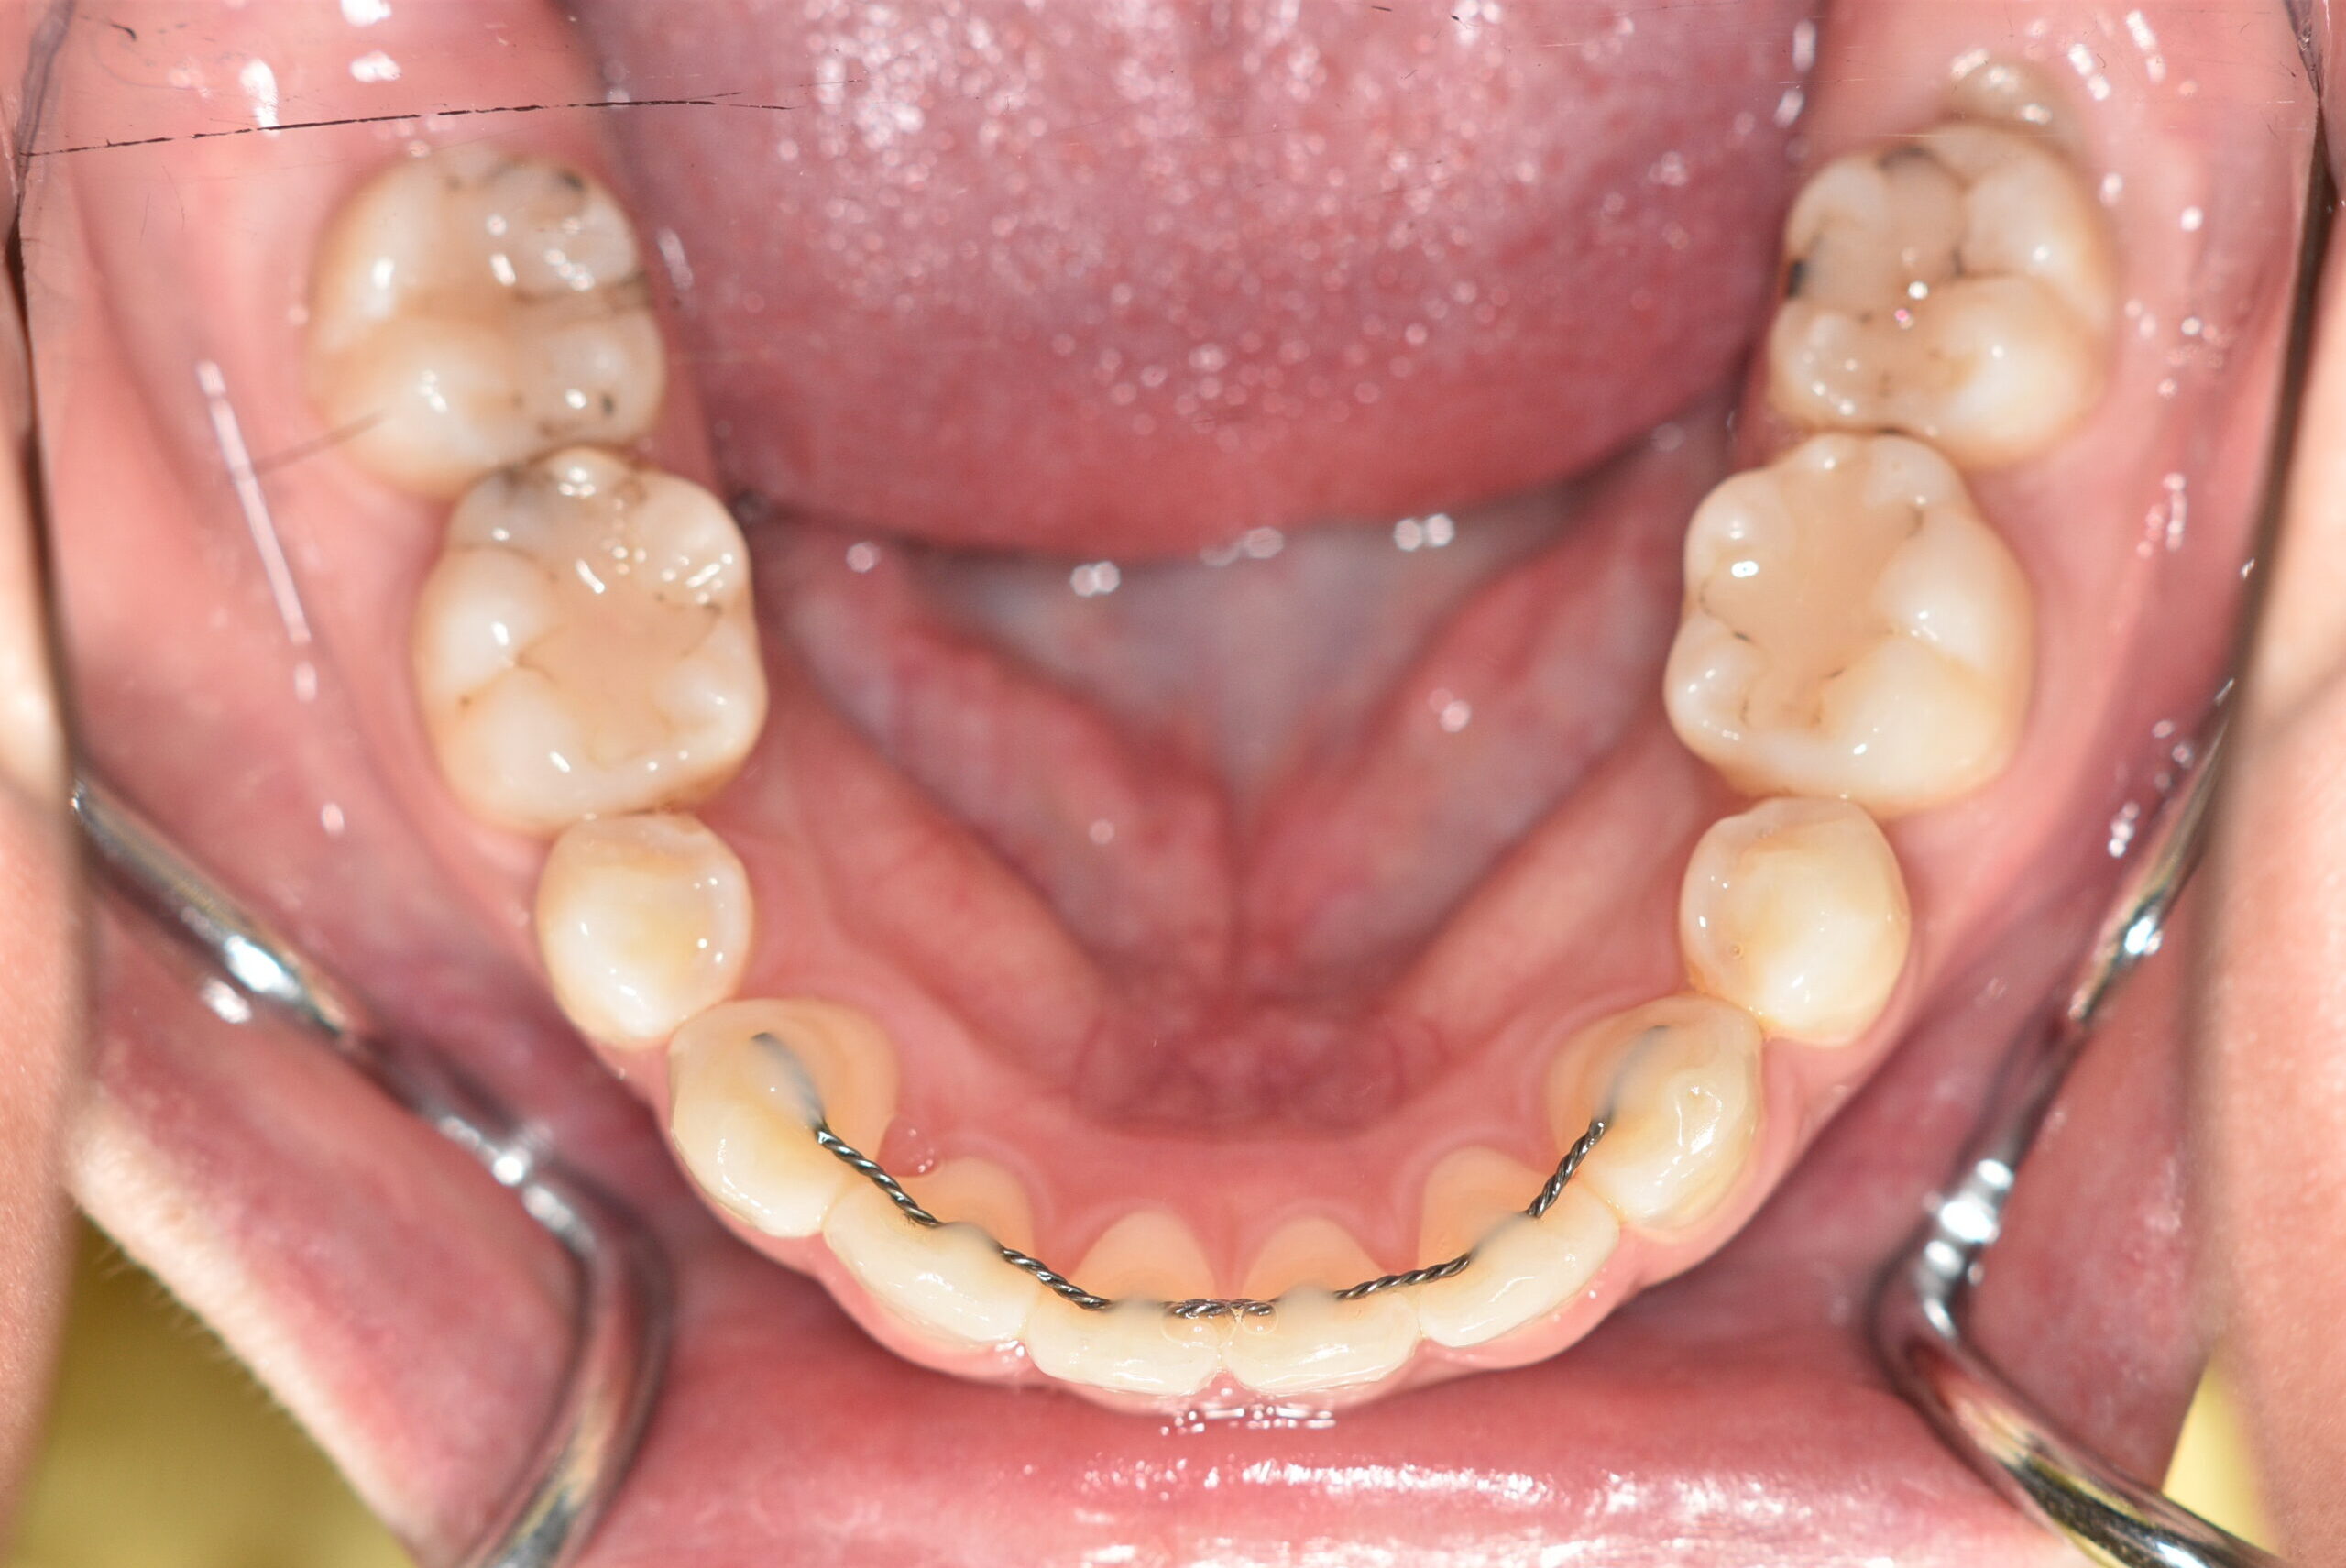

| 治療内容の詳細 | 初診時29歳の女性で、出っ歯を気にされ来院されました。 検査の結果、上顎前突を伴うアングルⅡ級1類不正咬合と診断しました。 治療としては、上顎左右第1小臼歯および下顎左右第2小臼歯をして、セルフライゲーションブラケット装置(デーモンシステム)で歯の配列を行いました。 同時に顎間ゴムにて咬合関係の改善を行いました。 この際、上顎に歯科矯正用アンカースクリューを設置し上顎前歯部後退時の土台としました。 治療期間は、2年6ヶ月でした。 |